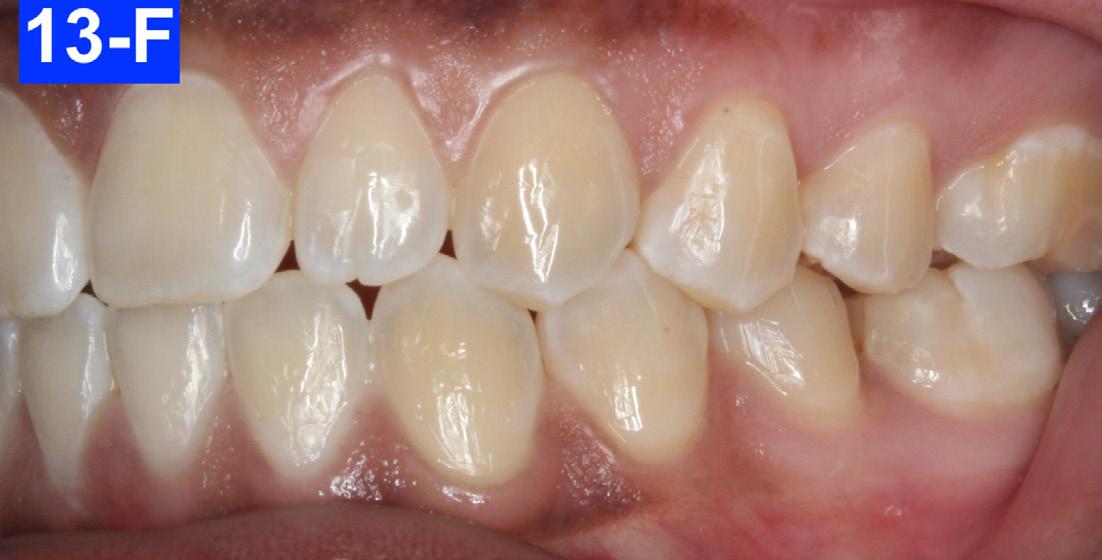

Fig. 13-F: 3 years post-treatment, left lateral view

The patient reported that she had not been wearing her retainer, no longer sucked her thumb, and no longer performed the OMT exercises (Figures 13A-O).

Figures 12-A to 12-M show the post-treatment images at the time of insertion of the retainers. We had an opportunity to evaluate the patient’s occlusion three years post-treatment. Compared to the initial post treatment evaluation, it was noted that the occlusion had settled into an even more stable position after three years.